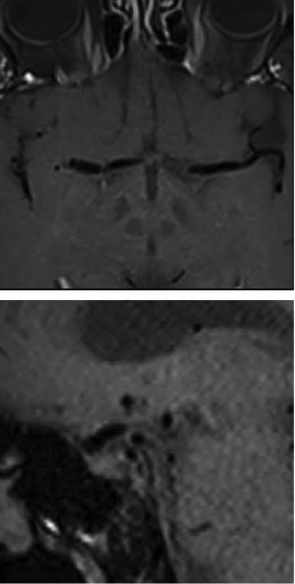

基于高分辨率黑血增强T1脂肪饱和加权血管壁成像平扫:

钆强化MR显示颈内动脉末端和双侧MCA同心圆强化:

因怀疑原发性中枢神经系统血管炎开始给予激素治疗,3个月复查强化消失: